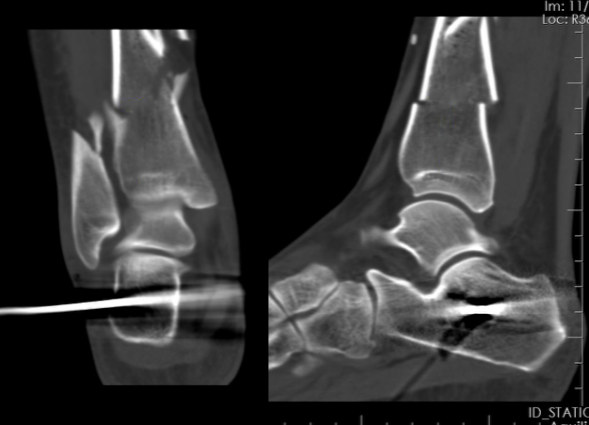

导读:不说废话,直接上图 !!!患者,女,50 岁,交通伤。诊断: 右胫腓骨开放性粉碎性骨折。胫骨后缘未见骨折,骨折线距踝关节平面不足 4 cm小腿下端前侧约 10 cm 创口,急诊清创...

患者,女,50 岁,交通伤。

诊断: 右胫腓骨开放性粉碎性骨折。

小腿下端前侧约 10 cm 创口,急诊清创,跟骨牵引,肿胀逐渐消退,白细胞、CRP、血沉等炎症指标降至正常范围。